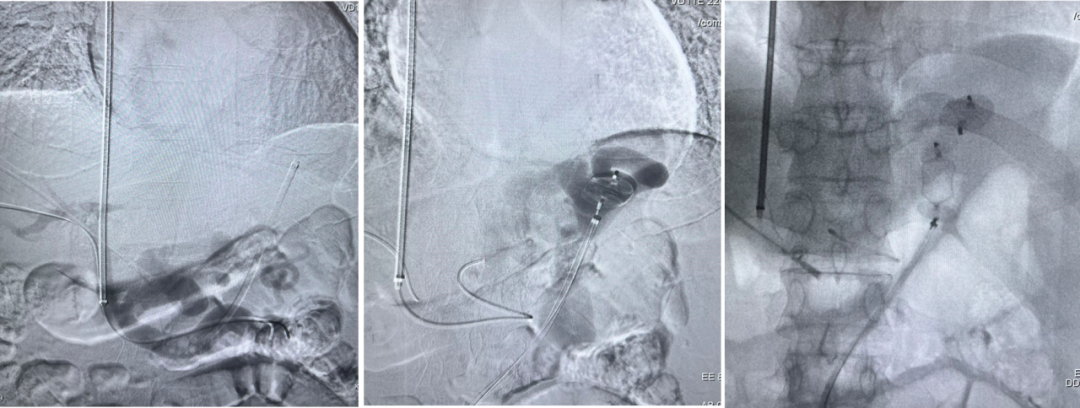

布加综合征(BCS)

对肝静脉闭塞型,直接穿刺下腔静脉建立 DIPS 通道;

对下腔静脉+肝静脉联合闭塞,先置入下腔静脉支架,再通过其作为“桥梁”完成 TIPS;

曾有一例19岁少女,每日需放腹水2000ml,术后当天腹水完全消退,疗效极为显著。

DIPSS-肝静脉闭塞(XJD)

肝静脉闭塞型

下腔静脉型合并消化道出血

下腔静脉型